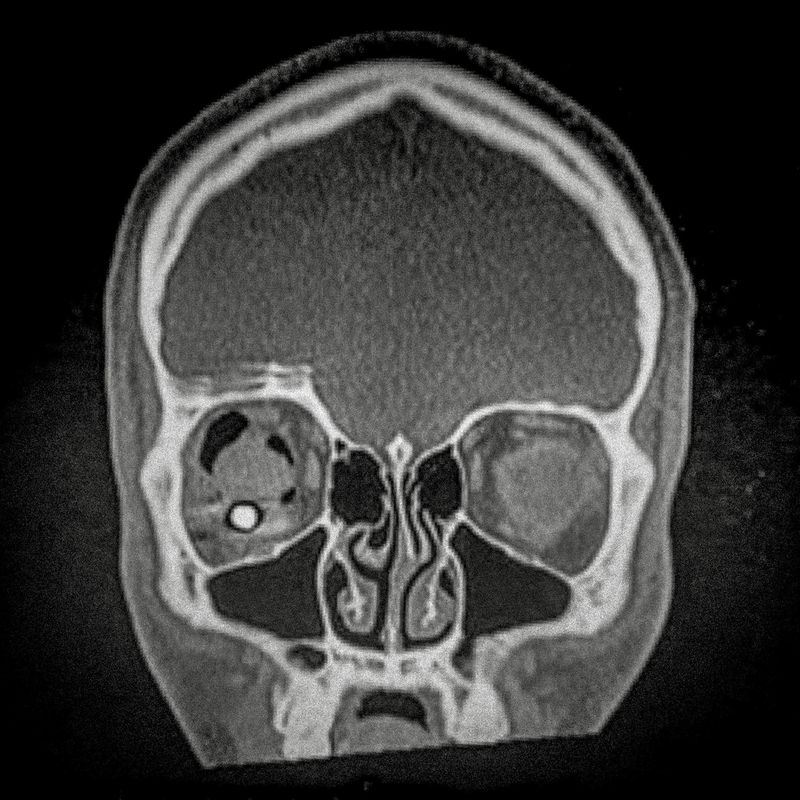

X-ray showing the pellet embedded in the skull of Ybar Soto (29) Ybar was hit by a pellet that lodged in his right eye on October 24, 2019 in Plaza Italia. Santiago. His diagnosis was ocular burst. Santiago, Chile. December 28, 2019

Ybar Soto (29) Electrical Technician Lives in Puente Alto,Santiago Ybar was hit by a pellet that lodged in his right eye on October 24th, 2019, at Plaza Italia, Santiago. His diagnosis was an eye burst. “If I would have shot the police in his eye, would they have me to signing once a month? I’ve had to face really hard situations, situations where I have seen the police looking at my face and laughing at me, because of the damage they did in my eye. What can I do against that? I can’t do anything. This is a huge anger and pain that is going to weigh me down my whole life. Until now I have the same answer. I do not regret for a fucking second going to protest that day because I am totally and absolutely convinced that we were not doing anything wrong. These are our rights.”